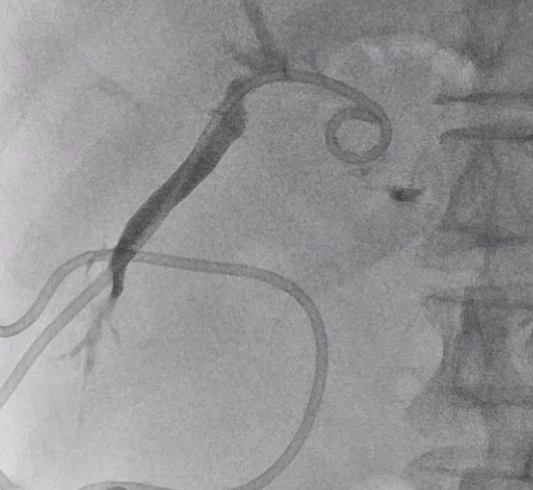

바늘을 통해 와이어를 넣고, 와이어를 따라서 배액관이 들어갑니다.

배액관은 지난 글에서 알려드렸던

이런 돼지 꼬리 모양의 카테터를 넣어 배액관이 잘 빠지지 않게끔 해줍니다. (이름도 돼지 꼬리 입니다.)